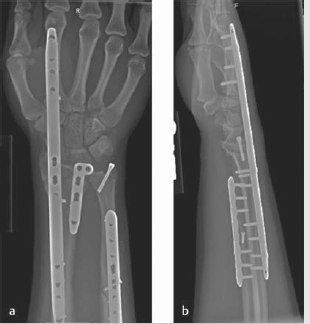

Although the original technique involved using a 3.5-mm plate on the floor of the 4th dorsal compartment to the 3rd metacarpal, 17 Hanel et al published a modification using either a Synthes 2.4 mm distal radius bridge plate or mandibular reconstruction plate through the 2nd dorsal compartment to the 2nd metacarpal (► Fig. 8.2). 16

The bridge plate functions as an internal fixator, reducing the fracture through ligamentotaxis.

Advantages include reducing the need for nursing care of pin site tracts on external fixators, relatively short operative time, and a stable wrist to allow early use of the upper extremity.

Immediate weight bearing through the forearm and elbow is permissible with a platform walker followed by transition to hand grip crutches at 1 month or so.

The plate is removed after fracture consolidation, an average of 112 days in Hanel’s series. 16